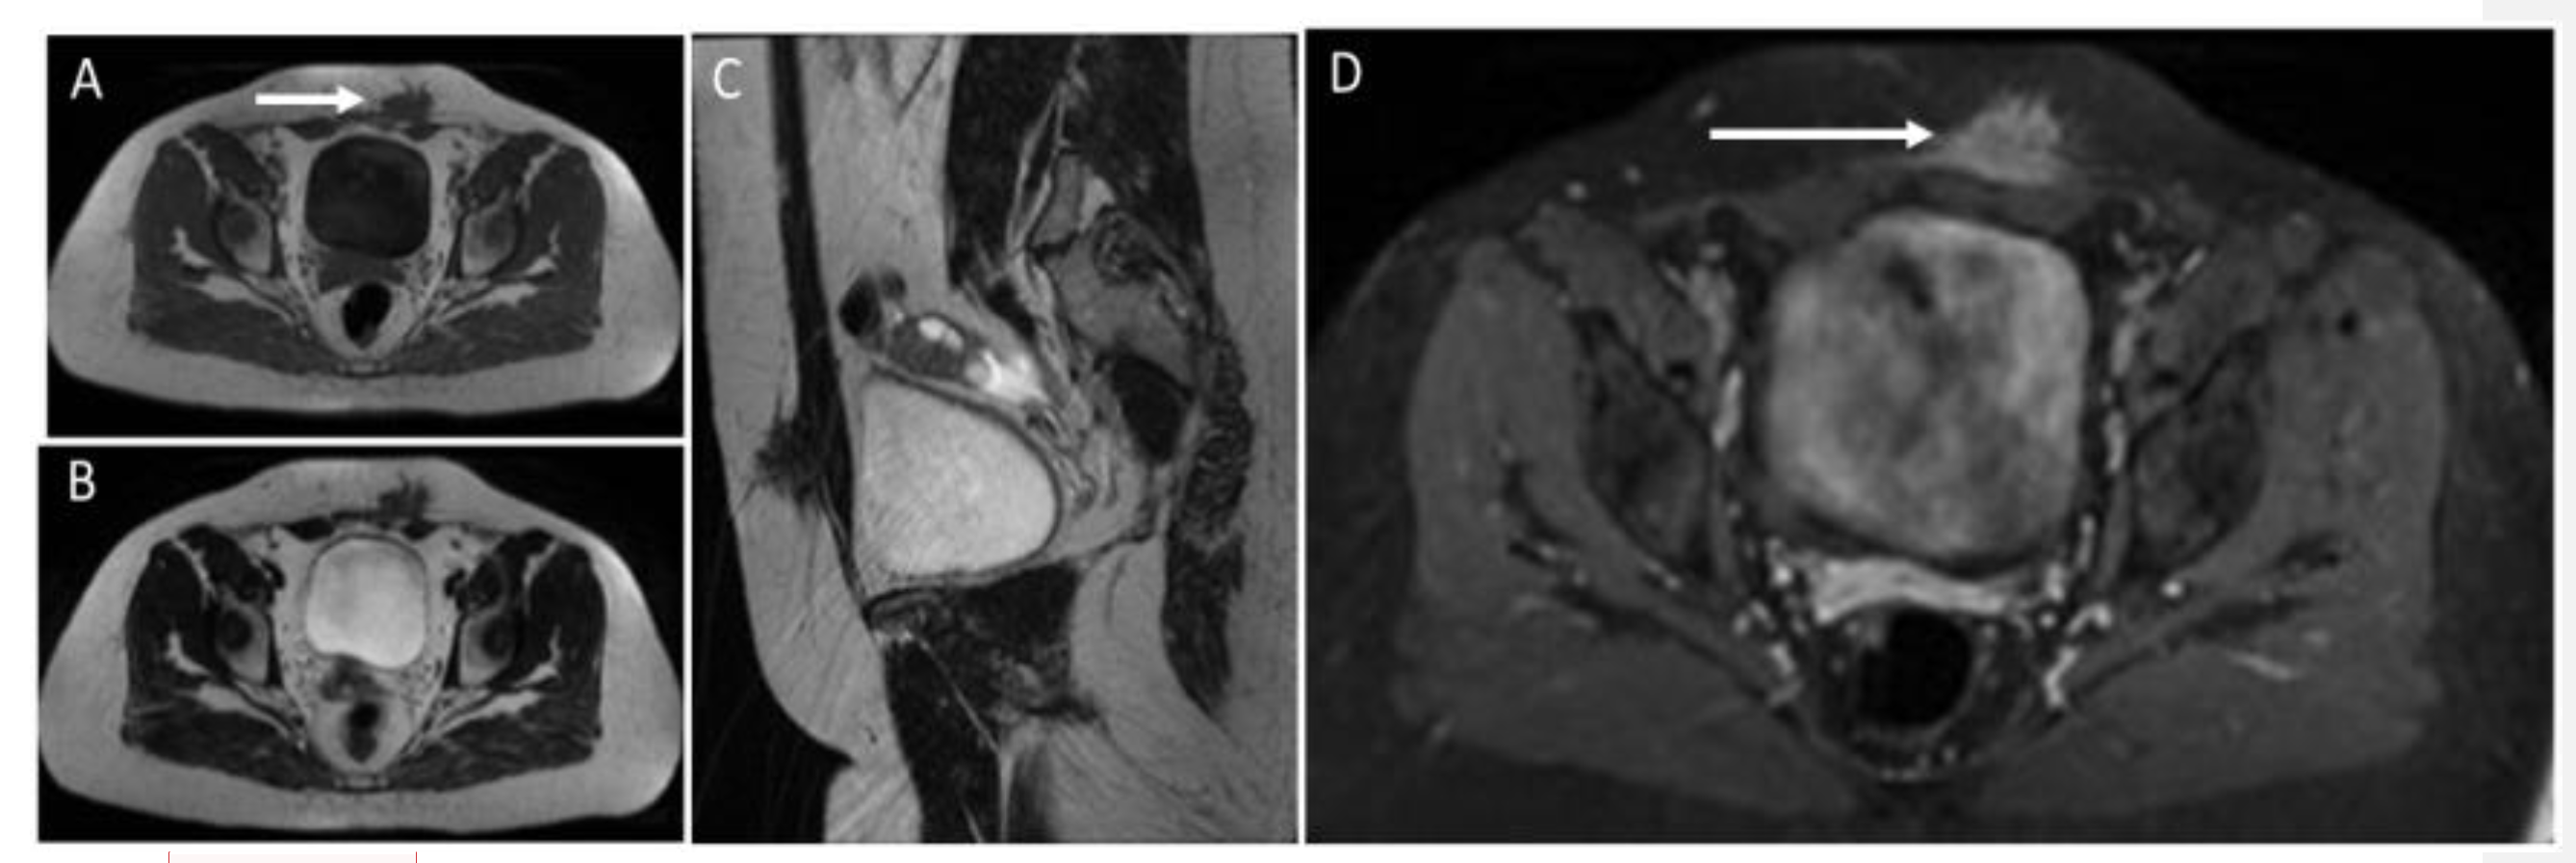

Figure 18. MR study of an endometriotic nodule (arrows) in the left rectus abdominis muscles and subcutaneous tissue. Endometriotic implants inside muscle are well characterized on MR. They show heterogeneously low signal on T1 (A) and T2 images (images B,C) and strong enhancement after the injection of contrast agent (D). Sagittal reconstruction (C) shows the extension of the endometriotic nodule into fat tissue, fascia, and intramuscular location.

US demonstrates heterogeneously hypoechoic, round or oval-shaped nodules or masses, with scattered internal echoes, and small cystic areas [9,50,53,54], surrounded by a hyperechoic rim [55] (Figure 17).

CT shows solid masses with ill-defined borders, isoattenuating to the surrounding muscles [55]. After contrast injection, endometriosis may show slight enhancement [50,53,54] and a characteristic “Gorgon sign”, corresponding to linear strands irradiating peripherally from the central nodules [55]. MRI provides excellent contrast resolution and demonstrates the depth of infiltration, gives better tissue definition, and shows the integrity of the surrounding muscle tissue [54]. On MR, abdominal endometriosis is hyperintense on T2-weighted images [50,54,55]; isointense to muscles on T1-weighted sequences, with foci of high signal, suggestive of hemorrhage [50,56]; and presents high signal lesions on fat-saturated T2-weighted images, with moderate enhancement [54,56] (Figure 18). In addition, diffusion-weighted imaging (DWI) may be useful for differentiating AWE from tumors. Regarding endometrial cysts, AWE tends to have lower apparent diffusion coefficient (ADC) values compared with other cysts, due to blood content [50]. However, compared to pelvic endometriosis, while the latter varies from purely cystic chocolate cysts to solid deposits or fibrosis, AWE will show almost invariably a pure solid aspect.